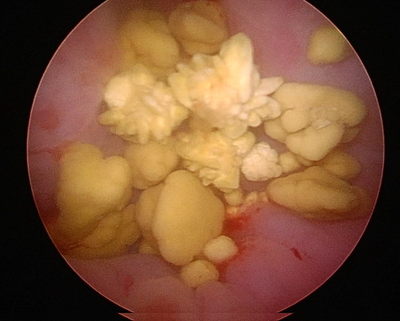

膀胱結石とその形状

レントゲン検査や超音波検査で見る膀胱結石は不鮮明な丸い石のことが多いとが思います。実際には膀胱結石には様々な種類があり、その形状や表面、色などは特徴が多い結石も含まれます。例えば同じストルバイトでもそれぞれに特徴があります。長期間膀胱内にあった結石は膀胱内で転がることで表面が削られてしまい、ツルツルになっていることもあります。このような患者さんでは症状は軽く、発見が遅れてしまう場合も見受けられます。

一方で表面に多くの突起があるようなストルバイト結石などもあります。このような場合にはこの棘が膀胱粘膜を傷つけてしまい、血尿や排尿痛などの症状が強く出ます。

猫の結石でも起こりえますが、犬の結石症でも複数の結石が認められ場合もあります。このような患者さんでは事前に膀胱結石の数が把握できないために開腹手術では取り残しを起こしやすいパターンとなります。内視鏡手術ではこのような患者さんでも非常に小さな結石でもカメラで確認しながら除去が出来ます。

また、丸い結石と棘のある結石が混ざって形成される場合もあります。尿検査ではストルバイト結石と診断されていたが、内科治療に反応しない場合などではこのように複数のパターンが起こっていることがあります。実際に摘出された結石による成分分析によって原因が明らかになることも認められます。